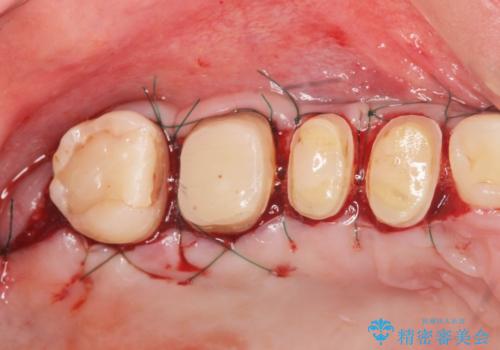

抜歯時に可及的に歯肉のボリュームを保つよう骨充填材とコラーゲン製剤による填塞を行い審美的かつ機能的なブリッジとなるよう治療を進めます。

- 66万円(ジルコニアクラウン×5・仮歯×5)費用は治療当時の料金となります